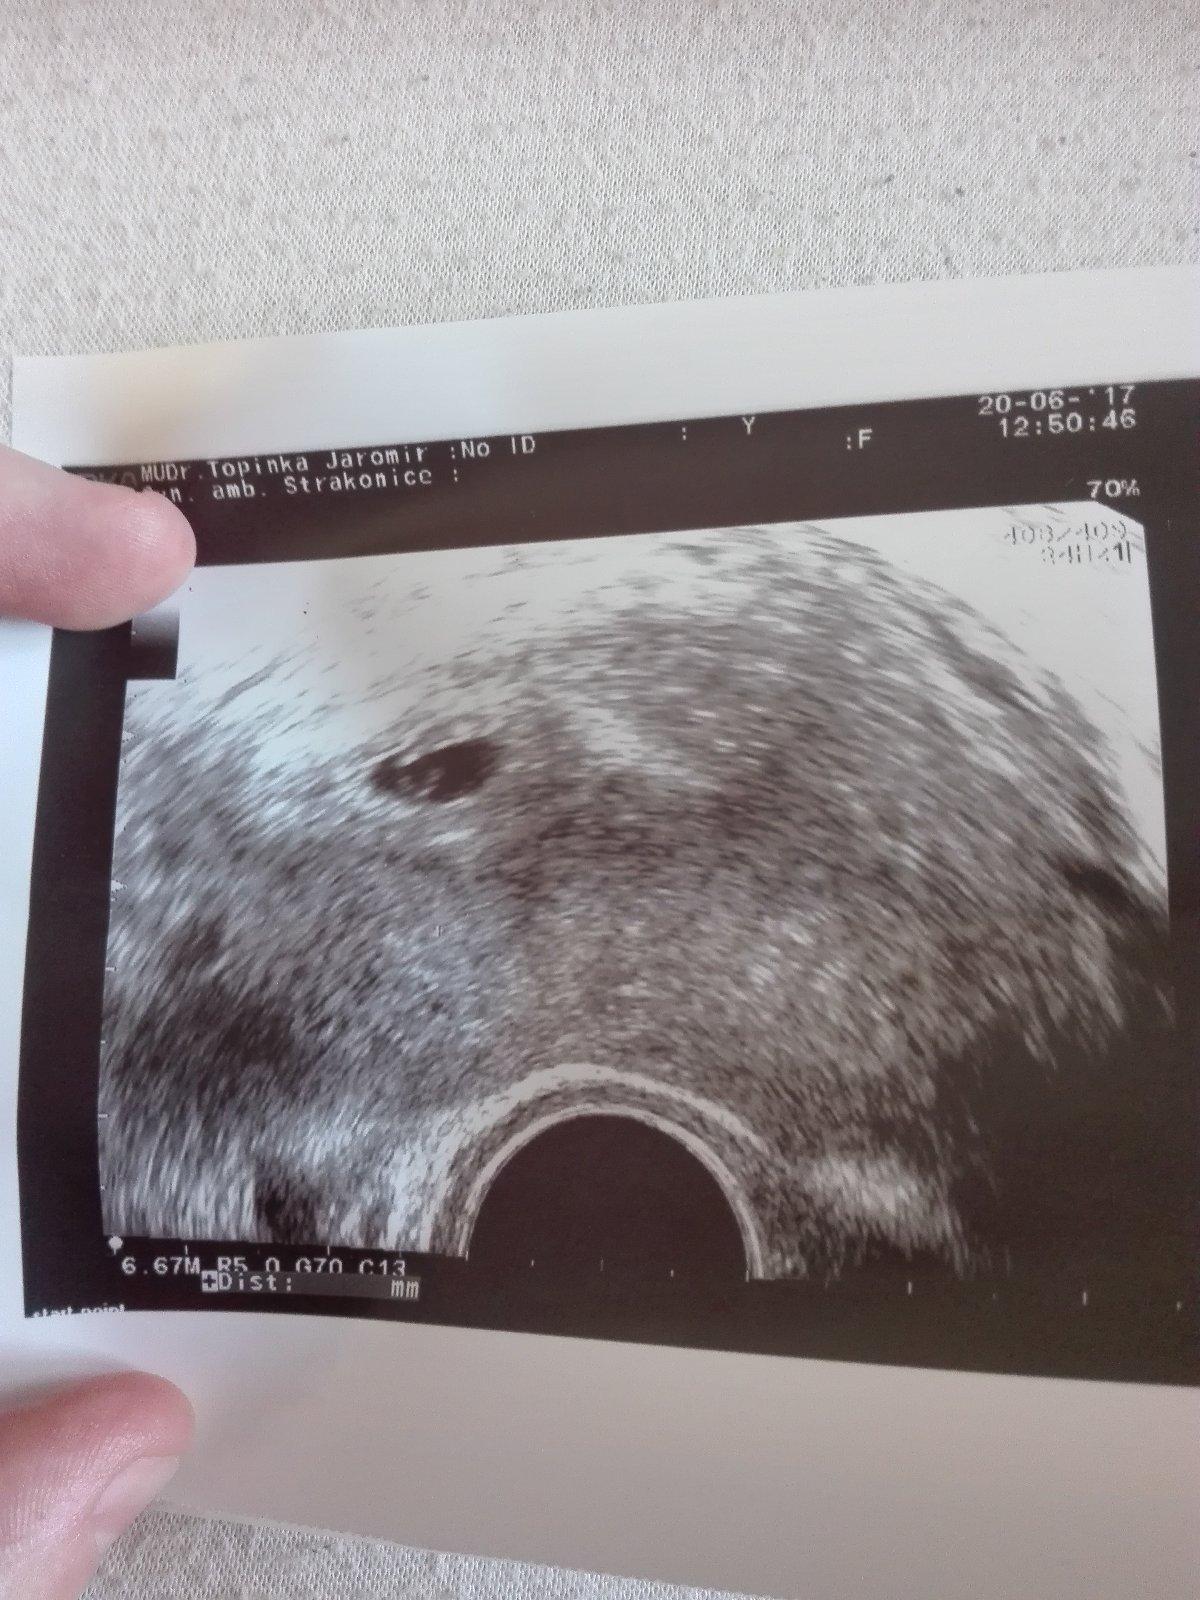

Tak jsem dopadla dobre, jsou tam dve dutinky, mozna tri 😲 ale dve zanikaji, kazdopadne ta jedna je jasne prosperujici i s vackem,jak psal pan doktor do zpravy ❤

@tereza1989 dekuji, jj jedno, ale to odpovida, pry se tohle bezne stava, rikal syndrom mizejiciho dvojcete

@danielle94 tak doktor ještě nemohl nic určitého říci,prý tím že mám cyklus 30-32dní tak je ještě brzo a nic není pořádně vidět,ale sliznice zvětšená a krásně prokrvaná a 2stejné váčky,ale prý se vše potvrdí pristi utery jdy jdu znova.uvidíme zda druhý vácek zustane ci ne. Takze o srdicku nemohla být teď ještě ani řeč. Jsem ráda ze se o to muzu podelit s vámi,protoze rodine nic rikat zatim nechci a ono to ze mě musí prostě ven